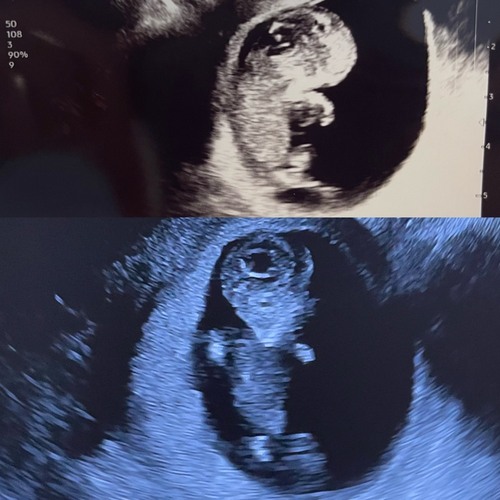

Iemand een idee?💙💖 Echo is van 11+3. Of is dit nog te vroeg en veranderd het nog te veel? Wat zijn jullie ervaringen?🥰

Iemand een idee? Termijn 12,2😊

12+3 dagen met 3d foto van de echo, wat denken jullie?

Volgensmij staat de nub in een hoek, en dat betekend een jongen😊

Iemand enig idee? 12+2 🩷💙